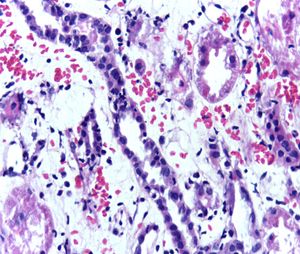

이식 후에는 기증 신장의 거부 반응을 억제하기 위해 면역 억제제를 평생 복용해야 한다. 가장 일반적인 약물 요법은 타크로리무스, 미코페놀레이트, 프레드니솔론 혼합물이다. 일부 환자는 시클로스포린, 시롤리무스, 아자티오프린을 복용하기도 한다. 이식 후 코르티코스테로이드를 피하거나 중단하면 조기 거부 반응 위험이 증가한다.[66] 1980년대에 처음 발견되었을 때 획기적인 면역 억제제로 여겨졌던 시클로스포린은 역설적으로 신독성을 유발하여 새로 이식된 신장에 의원성 손상을 입힐 수 있다. 타크로리무스도 신독성을 유발한다. 두 약물의 혈중 농도를 면밀히 모니터링해야 하며, 신기능 저하 또는 단백뇨가 있는 경우 거부 반응[67][68] 또는 시클로스포린, 타크로리무스 중독에 의한 것인지 확인하기 위해 신장 이식 생검이 필요할 수 있다.

면역 반응은 이식된 신장에 대해서도 발생하여, 거부반응을 일으켜 신기능 저하나 기능 상실의 원인이 될 수 있다.; 초급성기 거부반응

: 이식 직후부터 발생하는 초급성기 거부반응은, 공여자 항원에 대한 수혜자의 기존 항체가 이식 조직에 결합하여 일으키는 체액성 면역으로 생각된다.[160]

: 장기 허혈에 의해 이식 신장을 잃을 가능성이 높으며, 많은 경우 적출이 필요하다. 현재는 사전의 혈액형이나 HLA 항체의 적합성 검사에 의해 발생은 드물지만, 수혈에 의해 항체가 생성된 경우나 다차 이식의 경우에 발생할 수 있다.

; 급성기 거부반응

: 급성 거부반응은 이식 후 3개월 이내 정도에 일어나는 거부반응으로, 세포독성 T세포(킬러 T세포)의 지연형 반응에 의해 일으켜진다고 생각된다.

: 신장 이식에서 빈번하게 발생하는 거부반응이며, 스테로이드 펄스 요법 등의 강력한 면역억제 요법에 의해 많은 경우 정상적으로 기능하고, 예후는 장기 생착이 기대할 수 있다.

; 만성 거부반응

: 이식 후 3개월 이후에 발생하는 만성 거부반응은, 체액성 면역 외에, 면역억제제의 독성, 고혈압이나 고지혈증 등의 혈관 장애 등 여러 가지 영향이 생각되며, 자세한 병태가 알려져 있지 않고, 치료법도 확립되어 있지 않다. 면역억제제를 늘리거나 혈장 교환에 의한 항체 제거가 행해지는 경우도 있지만, 이식 동맥경화증, 이식편의 허혈이나 섬유화가 점차 진행되어 신기능이 저하된다.

기증 신장의 거부 반응을 억제하기 위해 면역 억제제가 사용된다. 이 약은 수혜자의 남은 생애 동안 복용해야 한다. 오늘날 가장 일반적인 약물 요법은 타크로리무스, 미코페놀레이트, 및 프레드니솔론의 혼합물이다. 일부 수혜자는 시클로스포린, 시롤리무스, 또는 아자티오프린을 복용할 수도 있다. 이식 후 코르티코스테로이드를 피하거나 중단하면 이식된 신장의 조기 거부 위험이 증가한다.[66] 1980년대에 처음 발견되었을 때 획기적인 면역 억제제로 여겨졌던 시클로스포린은 역설적으로 신독성을 유발하여 새로 이식된 신장에 의원성 손상을 입힐 수 있다. 유사한 약물인 타크로리무스도 신독성을 유발한다. 두 약물의 혈중 농도를 면밀히 모니터링해야 하며, 수혜자의 신기능 저하 또는 단백뇨가 있는 것으로 보이면 거부 반응[67][68] 또는 시클로스포린 또는 타크로리무스 중독에 의한 것인지 확인하기 위해 신장 이식 생검이 필요할 수 있다.